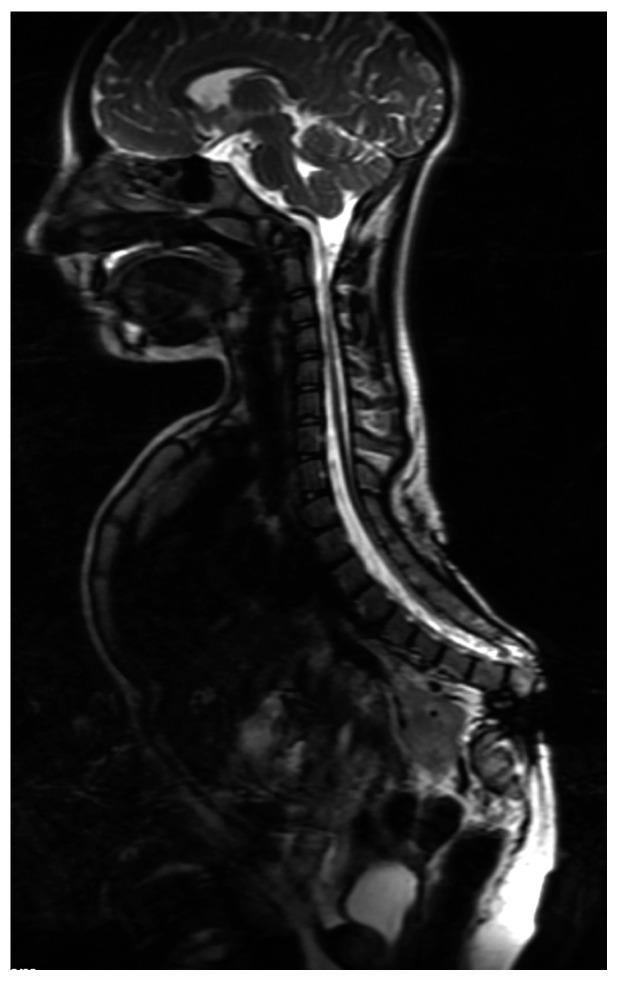

Abnormalities in cellular differentiation during embryo-fetal period may lead to various malformations of the spine. Caudal regression syndrome (CRS) is a group of defects with premature growth/development termination of the vertebral column. CRS can be divided into three types: sirenomelia, complete absence of the sacrum and partial absence of the sacrum. Genitourinary and gastrointestinal anomalies are common, with neurogenic bladder and bowel incontinence. Treatment of patients with CRS is complex and multidisciplinary and should be comprehensive. The most common orthopedic problems are: spinal deformity (kyphosis and scoliosis), spinopelvic instability and lower limbs deformities.

胚胎-胎儿期细胞分化异常可能导致脊柱的各种畸形。尾椎退化综合征(CRS)是一组因脊柱过早停止生长/发育而出现的缺陷。CRS可分为三种类型:美人鱼综合征、骶骨完全缺失和骶骨部分缺失。泌尿生殖系统和胃肠道异常很常见,伴有神经源性膀胱和肠道失禁。CRS患者的治疗复杂且需要多学科参与,应全面进行。最常见的骨科问题有:脊柱畸形(后凸和脊柱侧凸)、脊柱骨盆不稳定和下肢畸形。